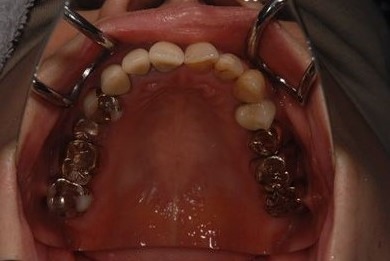

インプラントの症例写真 IMPLANT

骨再生スピードインプラント治療+セラミック治療

| 治療内容 | インプラント9本(抜歯即日スピードインプラント、サイナスリフト)、ハイブリッドセラミッククラウン12本(ハイブリッドセラミック用土台3本) | ||||||||||||||||||||||||||||||||